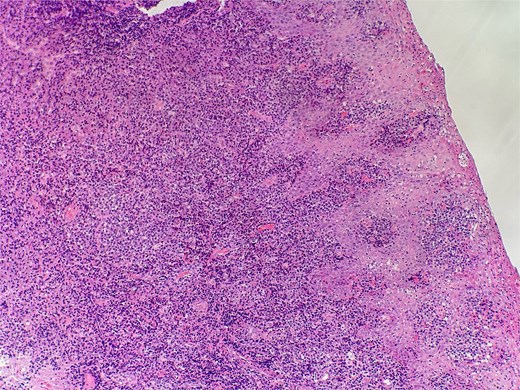

On clinical examination, harsh stridor with increased work of breathing was noted. Flexible nasoendoscopy demonstrated generalized supraglottic oedema with impending upper airway obstruction. Intravenous dexamethasone was commenced. A surgical tracheostomy with laryngeal biopsies under general anaesthetic was carried out. Histological examination (Figs 1 and 2) demonstrated hyperplastic, hyperkeratotic squamous mucosa with reactive atypia and an underlying dense polyclonal plasmocytic inflammatory infiltrate. No granulomata, prominent eosinophils, or stigmata of vasculitis were seen. Connective tissue disease screening demonstrated normal antinuclear antibody levels with positive perinuclear anti-neutrophil cytoplasmic antibodies. Anti-proteinase 3 levels returned as 3.7 IU/ml (range 0–1.9), while antimyeloperoxidase levels were normal. Rheumatology was consulted, and a provisional diagnosis of PCM was made. Serial laryngoscopy demonstrated resolution of the oedema, with the supraglottis regaining a normal appearance despite gradual tapering of the intravenous dexamethasone. A tracheostomy capping trial was successful. The patient was decannulated uneventfully and discharged on oral prednisolone. Three months later, he was maintained on 5 mg prednisolone—attempts to taper any further caused symptoms recurrence. Outpatient referral was made to Rheumatology for medical management with steroid-sparing therapy. Unfortunately, the patient was lost to follow-up due to failure to attend for outpatient review.

Slide from epiglottis specimen at index presentation showing squamous mucosa and underlying polyclonal plasmocytic infiltrate.

Slide from index presentation under higher magnification again demonstrating plasmocytic infiltration.